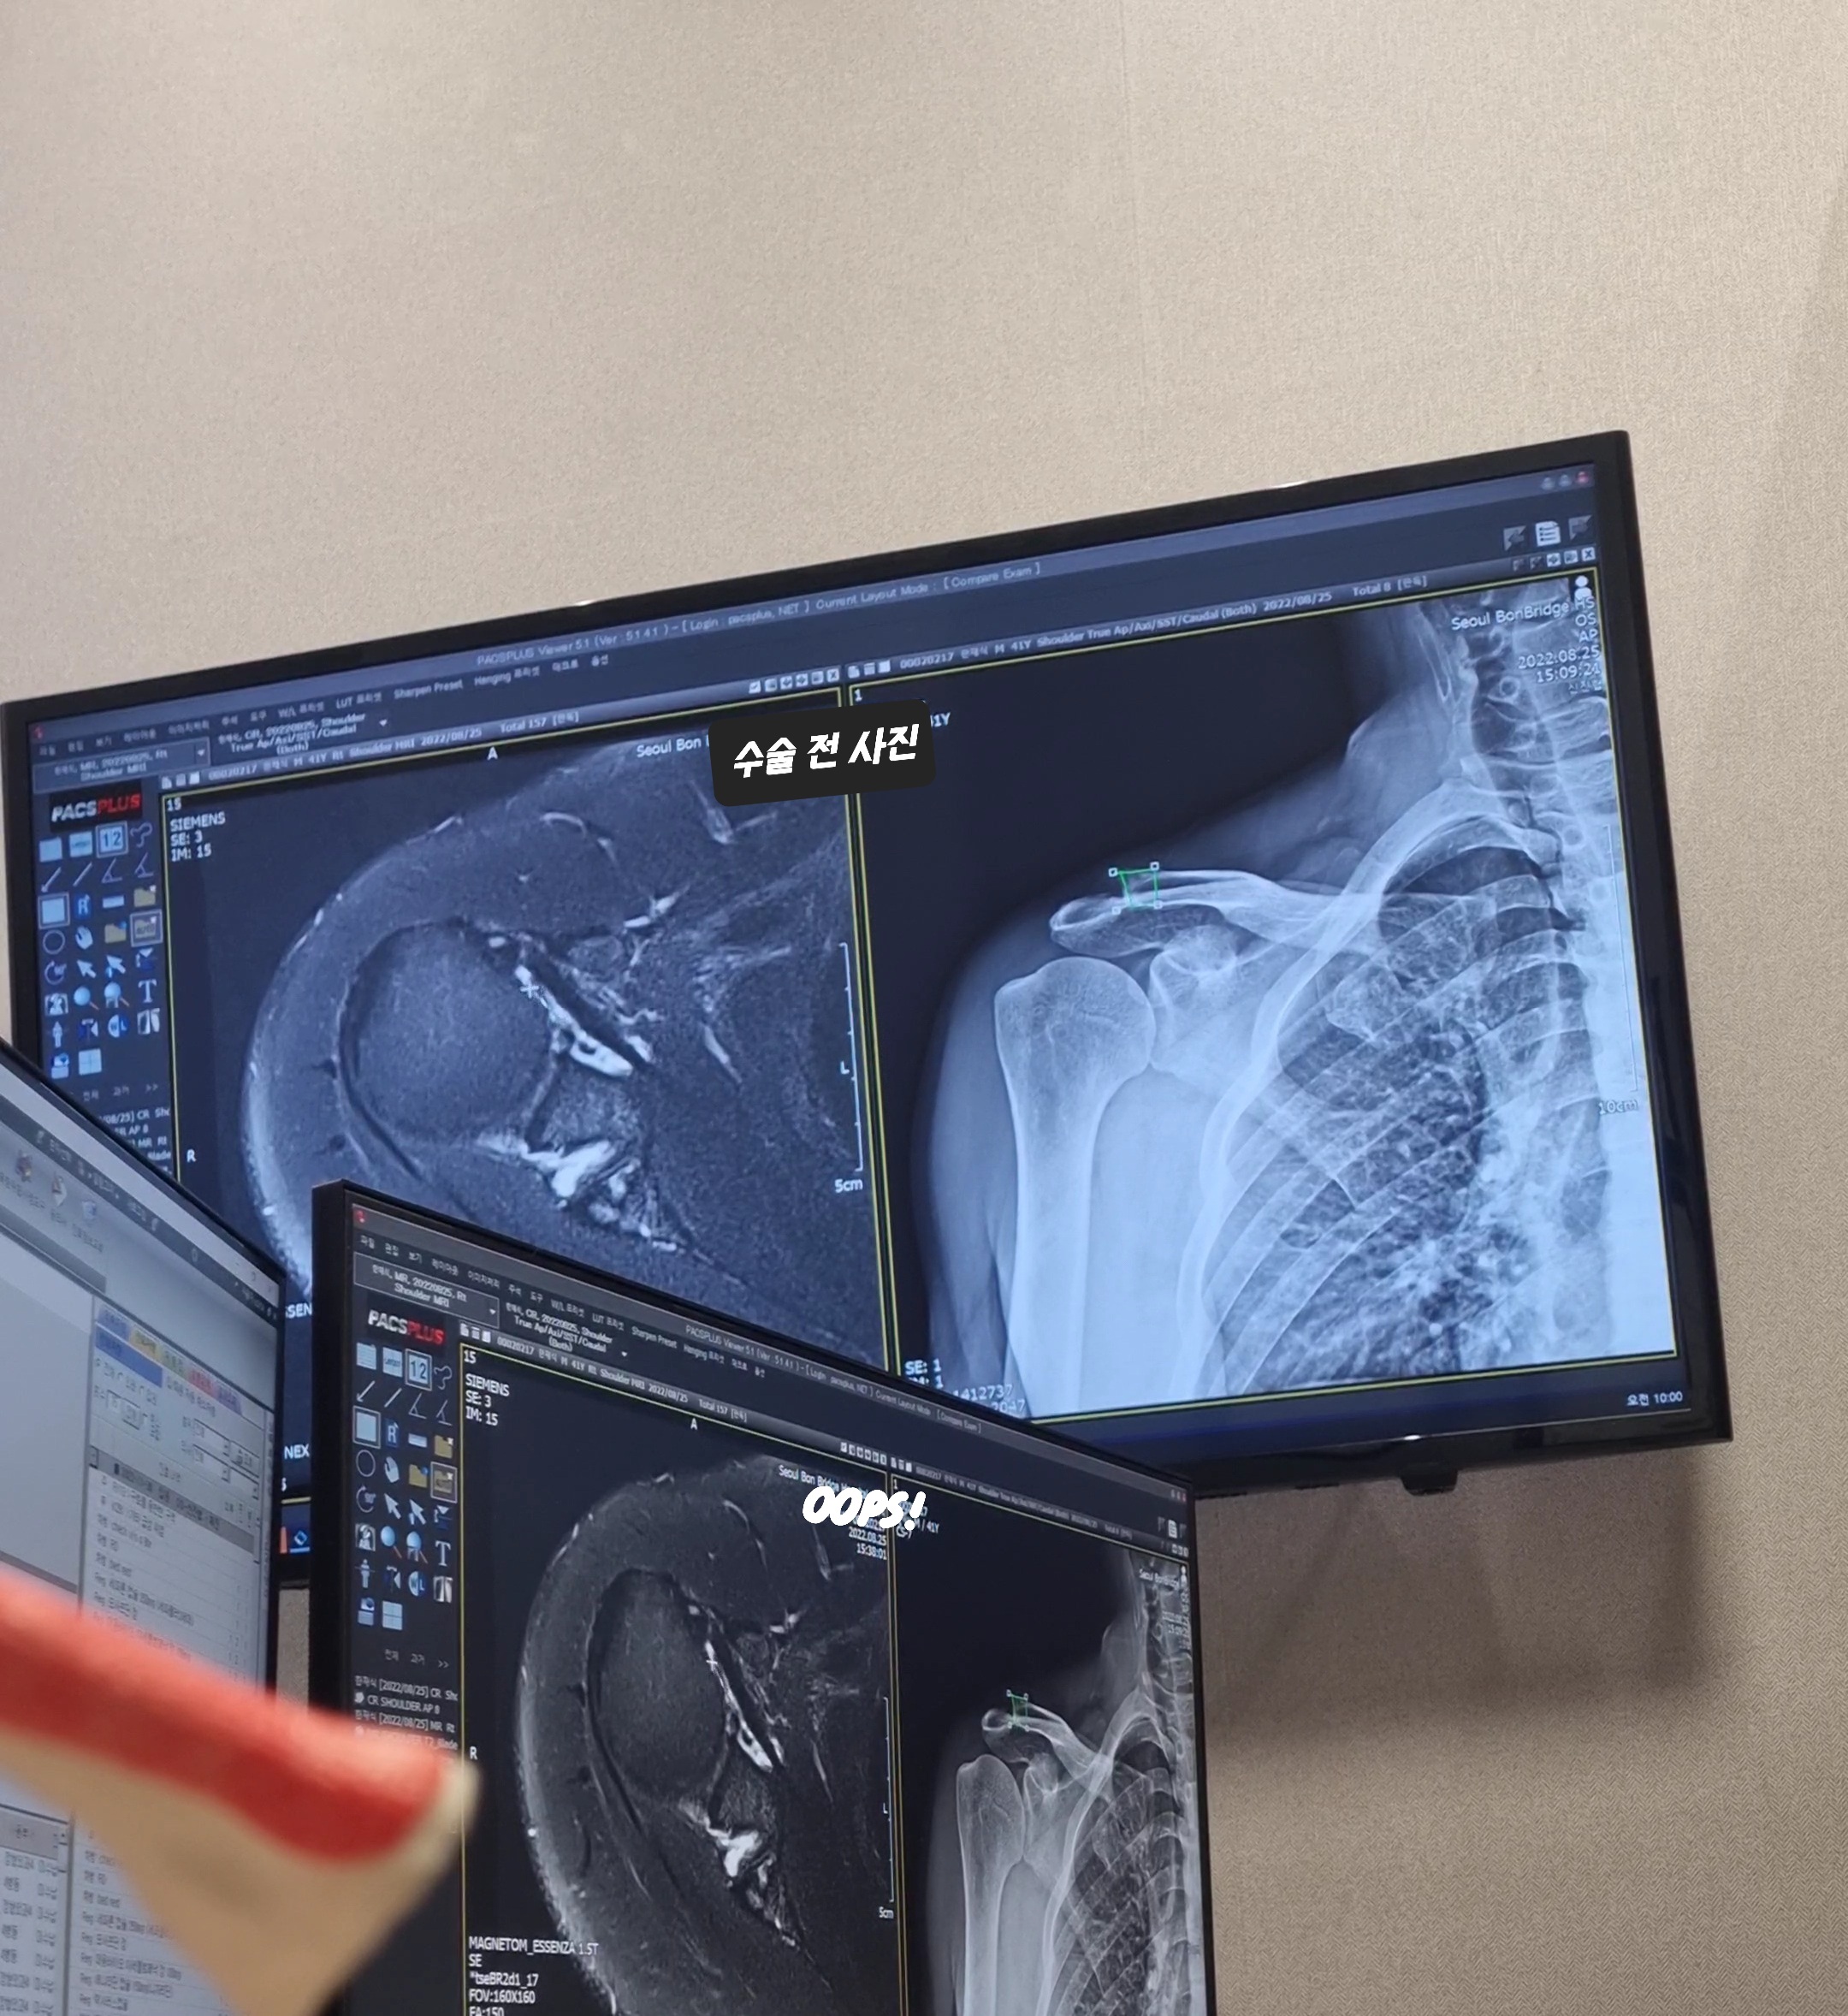

원장님과 진료를 하며 증상을 얘기 했더니 일단 mri를 다시 찍어서 상황을 보자고 하셨다. 8월에 찍은 사진이 없어 11월에 찍은 사진으로 당시 설명을 대신해 본다.

수술 전에 찍은 mri와 엑스레이 사진이다. 엑스레이 사진을 보면 견쇄관절 부분에서 견봉과 쇄골이 너무 가까워 뼈끼리 맞물려 염증을 유발하고 있었다. 저 사이에 연골이 있어야 하는데 어릴 때부터 많이 사용을 해서 닳아 없어졌다고 한다. mri 사진을 보면 군데군데 희끗한 게 보이는데 힘줄은 까맣게 보여야 좋은 것이기에 이상이 있는 것이다.

mri상에서 견쇄관절 위치를 보면 하얗게 염증이 일어나 있는 것을 볼 수 있다. 뼈에 염증이 생겼고 이 뼈들이 걔속 부딪치며 서로를 긁고 있기에 통증이 지속되었던 것이다. 그리고 왼쪽 어깨와 마찬가지로 견갑하근이 파열되었으며 작년 2월에 찍었을 때보다 손상 범위가 더 넓어져 있었다.